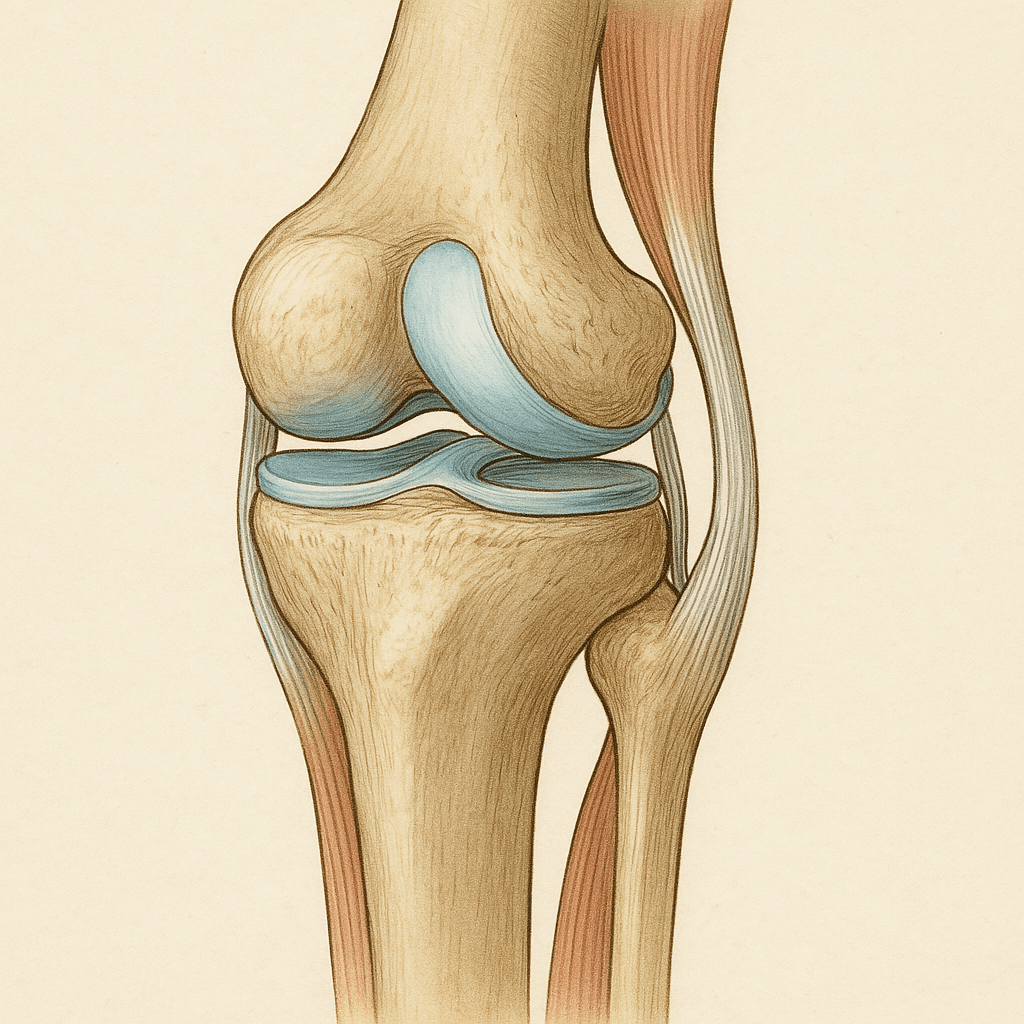

콘드로이친(Chondroitin)은 연골의 주요 구성 성분 중 하나로, 관절의 탄력성과 유연성을 유지하는 데 핵심적인 역할을 합니다. 우리 몸에서는 자연적으로 생성되지만, 나이가 들면서 점차 줄어들게 됩니다.

콘드로이친은 관절 속 **윤활유 역할을 하는 ‘관절액(활액)’**의 농도를 유지하는 데 도움을 줍니다.

관절액이 부족하면 뼈와 뼈가 직접 마찰을 일으키며 통증과 염증이 생기게 되는데,

콘드로이친은 이 윤활유를 보충하고, 마찰을 줄여줘서 통증을 완화하는 효과가 있어요.특히 골관절염 초기 환자에게 통증 완화 효과가 입증된 바 있고, 일부 연구에선 **비스테로이드성 소염제(NSAIDs)**를 줄이는 데도 도움을 준다고 알려져 있습니다.

2. 연골 재생 및 보호

연골은 혈관이 없는 조직이라 한 번 손상되면 스스로 회복이 잘 되지 않아요.

콘드로이친은 연골의 구성 성분인 프로테오글리칸과 콜라겐의 생성을 촉진하고,

파괴 효소의 작용을 억제해서 연골의 퇴화를 늦추거나, 회복을 돕는 역할을 합니다.즉, 단순한 보호를 넘어 재생을 유도하는 데에도 도움이 될 수 있다는 거죠.

3. 관절 유연성 증가

무릎, 손목, 어깨 등 자주 사용하는 관절의 움직임이 뻣뻣해지는 건

연골 사이의 쿠션 역할이 약해지기 때문이에요.

콘드로이친은 이 쿠션을 보강해줘서 관절 사이의 움직임을 부드럽게 해줍니다.특히 계단 오르기, 쪼그려 앉기, 오래 걷기 같은 일상 동작에서